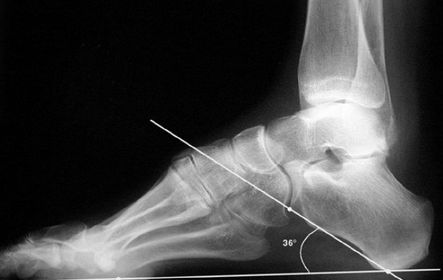

| What is this angle called? What is normal? What does an increased angle indicate? | Talo-calcaneal angle. 25-45 degrees. Increased angle = hindfoot valgus |